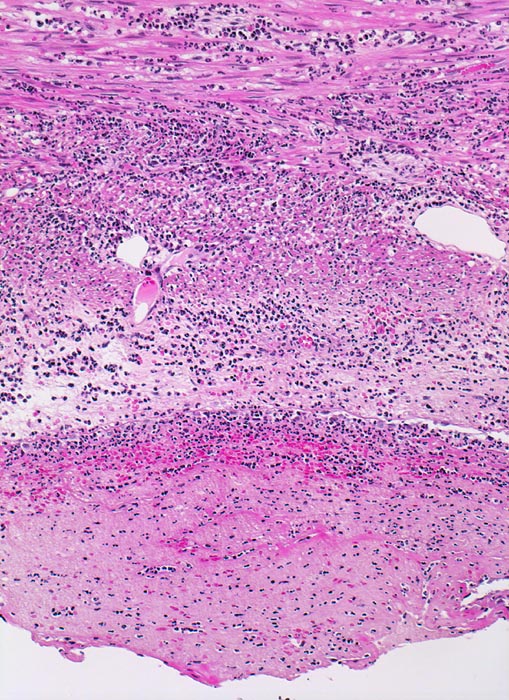

akute Appendizitis: fibrinös eitrige Peritonitis

Das Peritoneum unten im Bild wird bedeckt von einer dicken Schicht bestehend aus neutrophilen Granulozyten und Fibrin. Die Muscularis propria der Appendix zeigt ein phlegmonöses Entzündungsinfiltrat.